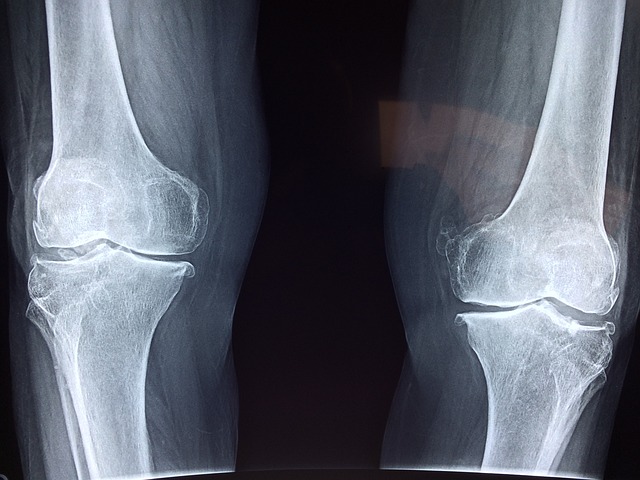

우리의 관절과 뼈는 우리가 일상적인 활동을 수행하고 삶을 즐기는 데 중요한 역할을 합니다. 그러나 현대의 불규칙한 생활 양식과 고용량의 스트레스로 인해 관절과 뼈의 건강에 대한 관심이 증가하고 있습니다. 이 블로그에서는 건강한 관절과 뼈를 유지하는 올바른 영양소, 규칙적인 운동, 체중 관리, 충분한 휴식과 수면에 대해 자세히 알아보겠습니다.